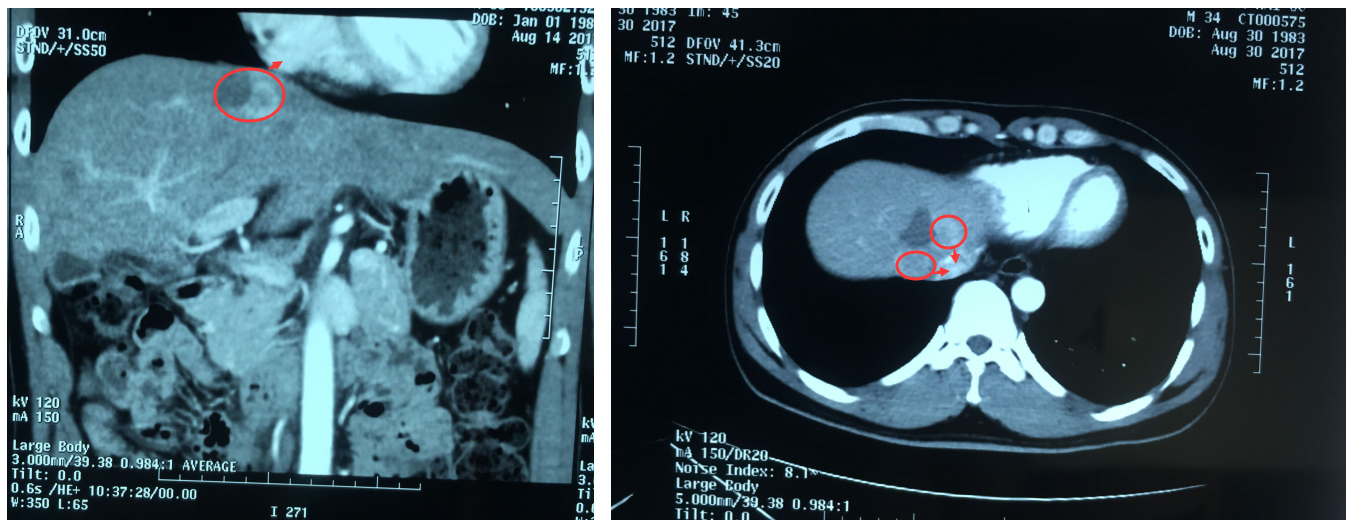

更让人心痛的是,经检查,他的肝脏肿瘤位置非常特殊:不仅位于膈脚下腔静脉旁,而且距离心脏只有1.5cm,不宜再行传统外科手术。常规肿瘤消融术又不足以彻底消灭肿瘤,那该怎么办呢?

▲患者肝脏肿瘤距离心脏1.5cm,位于膈脚下腔静脉旁

2017年9月1日上午,阮先生在气管插管全身麻醉状态下进行了纳米刀消融术,由白海山主任主刀,在CT扫描定位下,将两支电极针穿刺至患者肝脏肿瘤内进行消融。